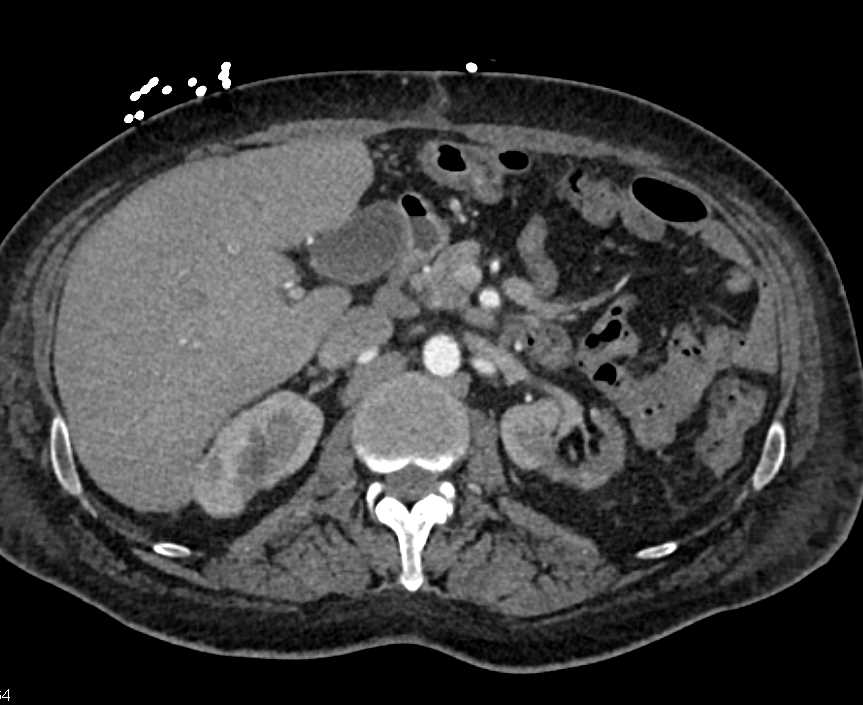

Dilated Small Bowel with Cinematic Rendering